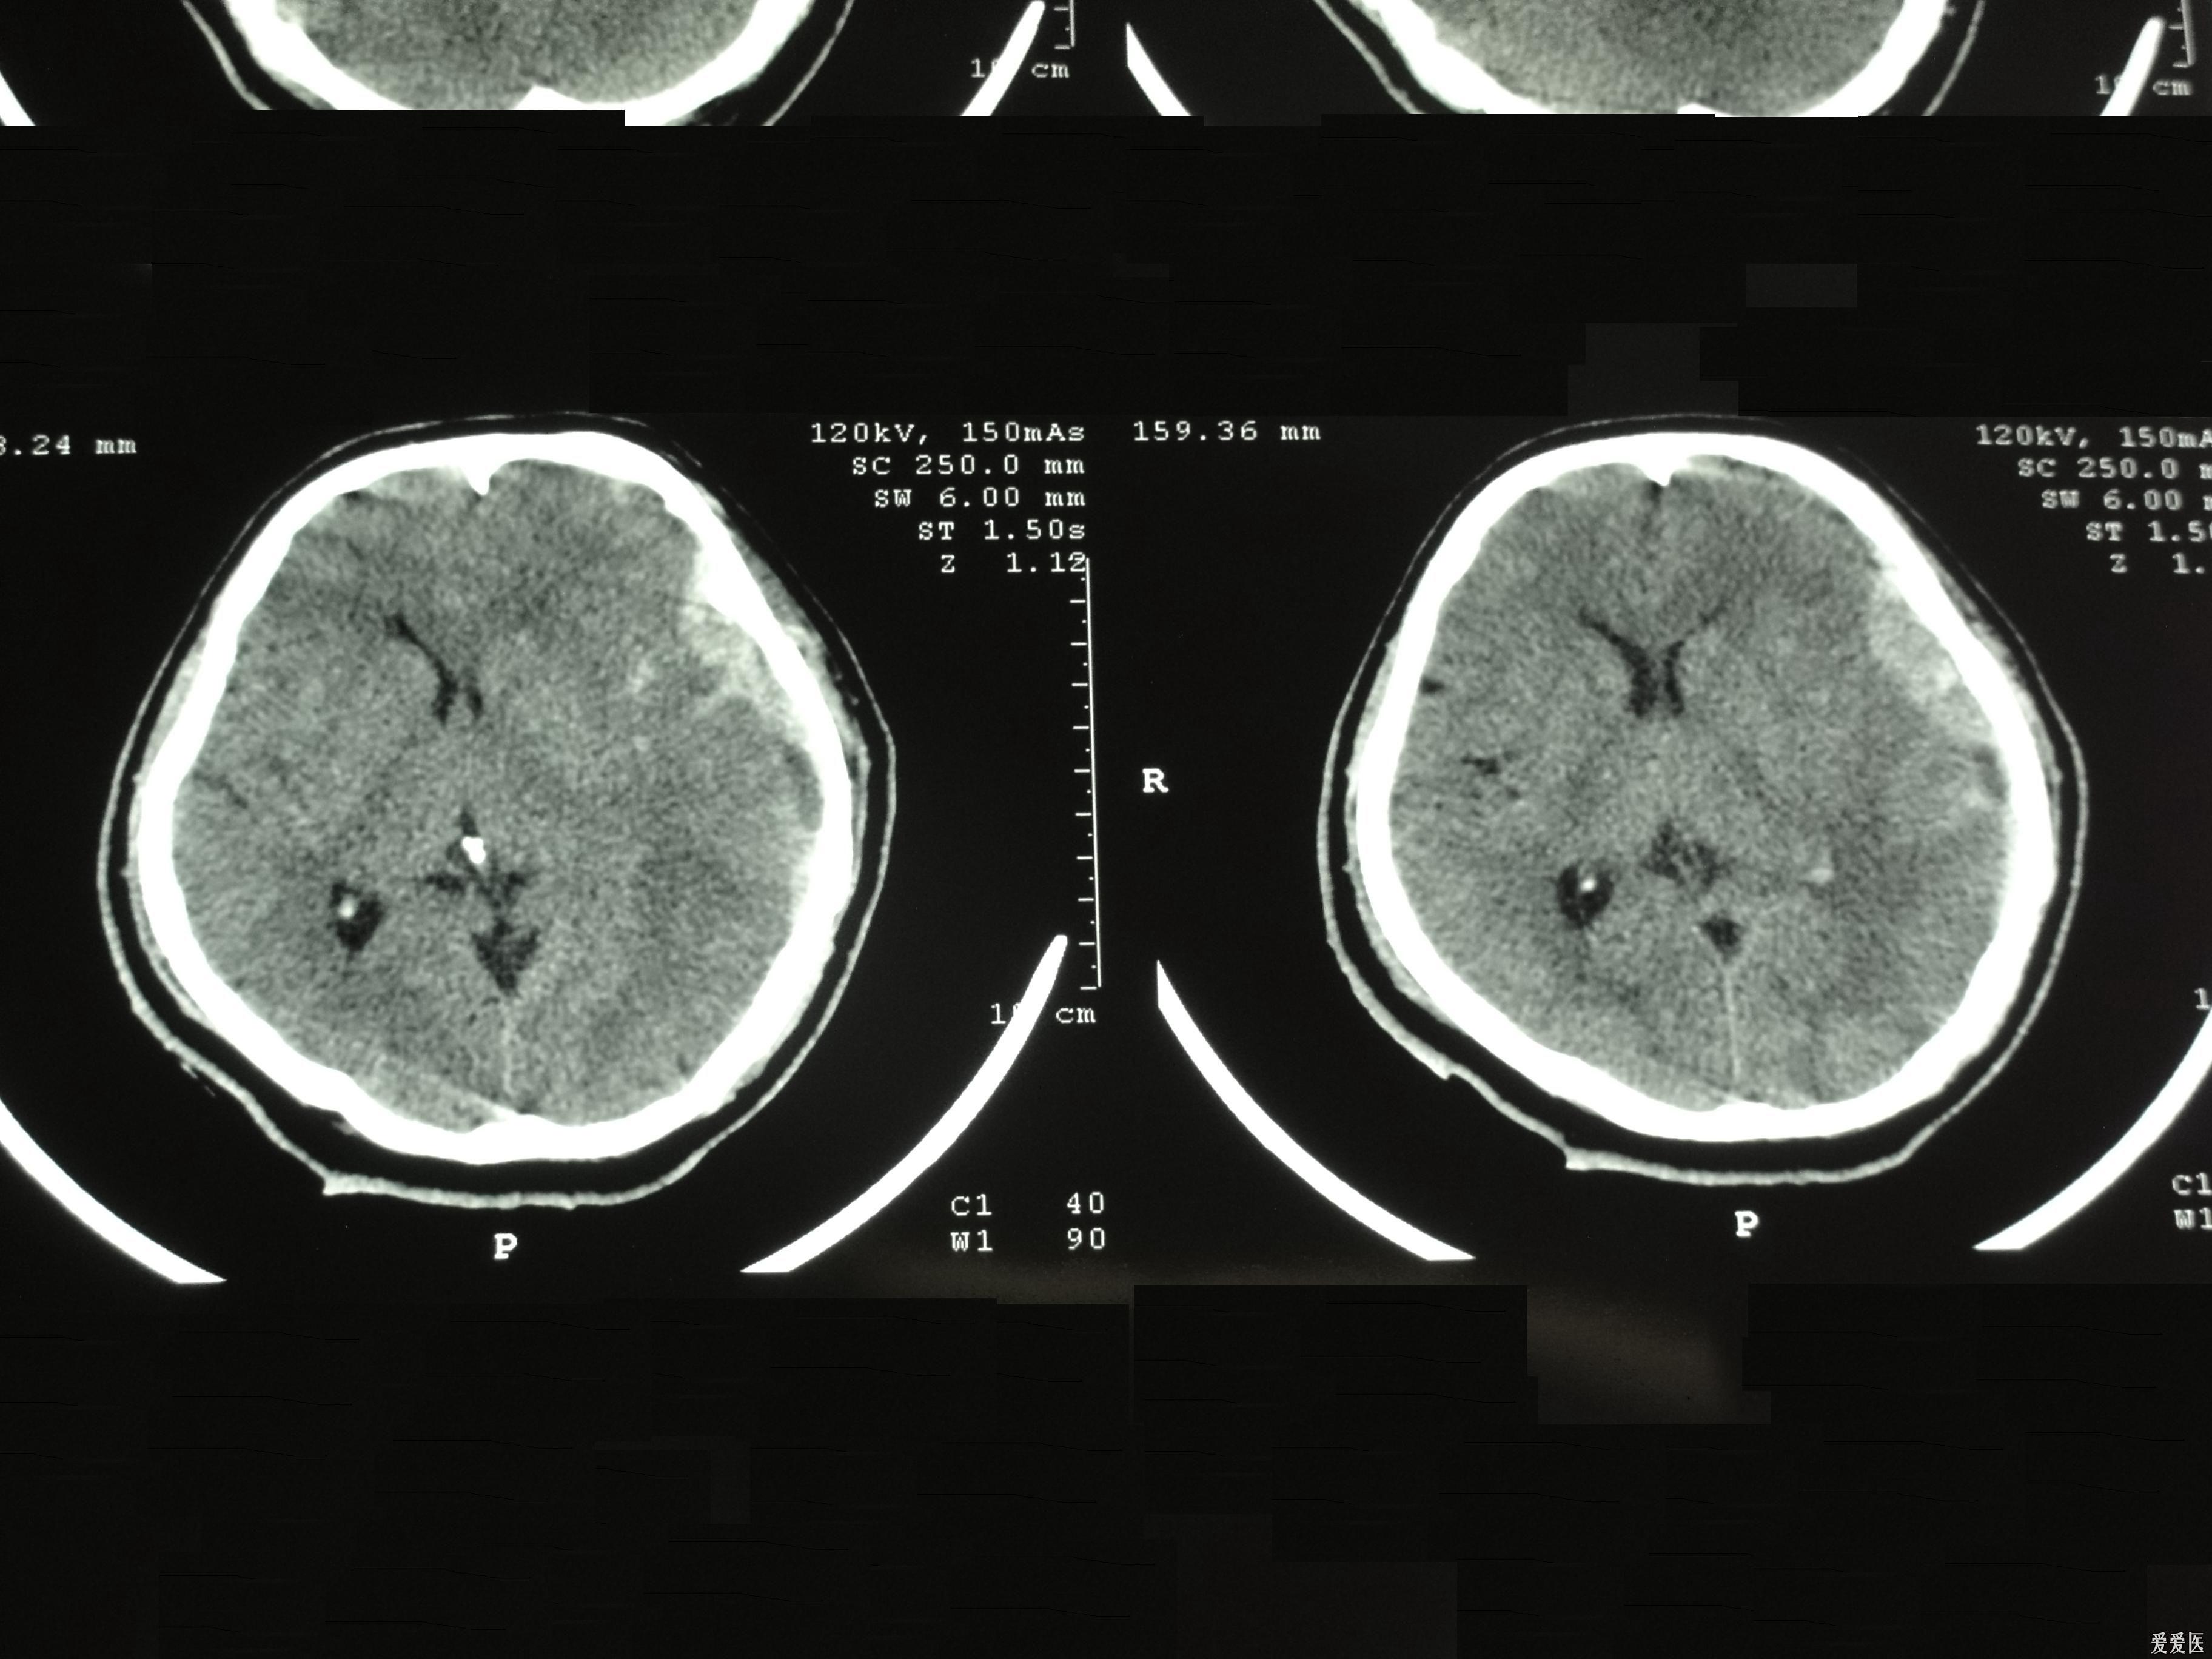

硬膜外血肿

图片尺寸3264x2448